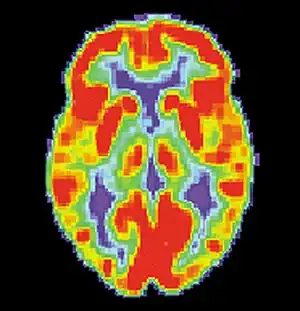

Brain positron emission tomography

Brain positron emission tomography is a form of positron emission tomography (PET) that is used to measure brain metabolism and the distribution of exogenous radiolabeled chemical agents throughout the brain. PET measures emissions from radioactively labeled metabolically active chemicals that have been injected into the bloodstream. The emission data from brain PET are computer-processed to produce multi-dimensional images of the distribution of the chemicals throughout the brain.[1]: 57